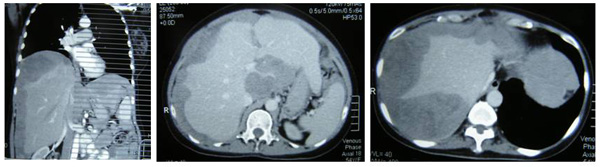

SH said she was well all these years and her progress was monitored by her doctor. About 10 years later, in early 2009, SH developed shortness of breath. She could not lift her left arm. She was tired and lost her appetite. A chest X-ray indicated large left pleural effusion. SH had the fluid in her lung tapped out. A CT scan on 7 January 2009 indicated several subcentimeter nodules in her left lung. The lymph nodes in the left axilla and aortopulmonary window were enlarged. Impression: left pulmonary and pleural metastasis.

SH sought a second opinion from another oncologist at a university hospital. Another CT scan was performed and it also confirmed a metastatic breast cancer with left pleural effusion with small benign liver cysts.

In August 2011 SH developed shortness of breath again. A CT scan on 4 August 2011 confirmed presence of mild left pleural effusion. Fluid was tapped out of her lung again.